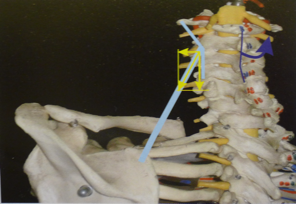

Frecce blu: risultante complessiva dell’azione degli elevatori del moncone della spalla e dei fasci superiori del gran dorsale.

Frecce rosa: azione dei fasci costo omerali del gran dorsale.

Frecce verdi: azione dei fasci inferiori del gran dorsale.

Frecce azzurre: azione dei fasci medi del trapezio e romboidi.

Frecce gialle: azione del dentato anteriore.

Il quadro associato avrà potenzialmente sullo stesso emilato le seguenti caratteristiche scheletriche, non necessariamente tutte presenti, per azione muscolare diretta:

- scapola elevata ad addotta

- clavicola ascendente

- lateralizzazione dell’osso ioide

- convessità laterale toracica nel quadrante superiore (sopra D7)

- convessità laterale toracica nel quadrante inferiore (sotto D7)

- elevazione dell’emibacino

- postero-rotazione dell’emibacino